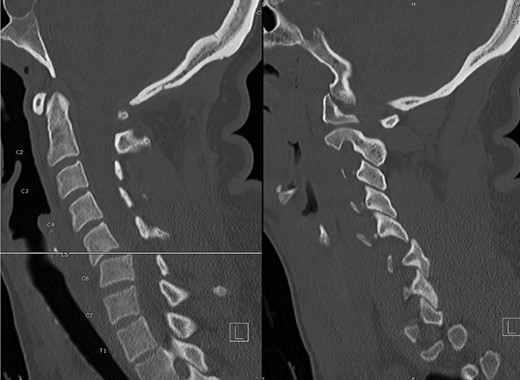

A computed tomography (CT) of the cervical spine without contrast revealed a C5-6 fracture dislocation and subluxation (Fig. 1) with spinal cord compression. The injury also included a posterior ligamentous complex rupture at C5-6, with fracture of the posterior lamina of C5 and right-sided jumped facet.

Preoperative CT, sagittal images through the center (left) and right side (right), illustrating the C5-6 fracture-subluxation and right jumped facet.